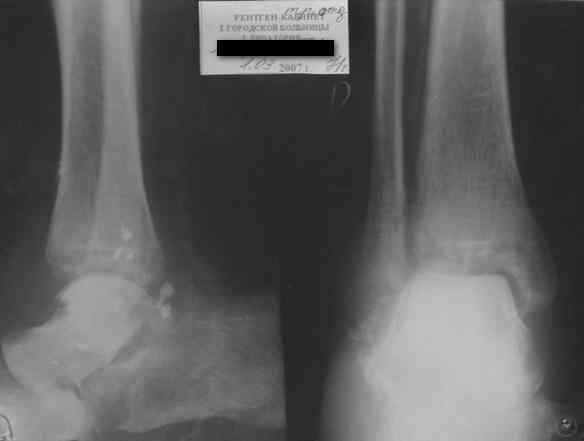

Уважаемый Александр! Как обещал представляю Р-граммы и операционные фото.

Последний снимок

Мнение по поводу тарана? АН есть?

> Мнение по поводу тарана? АН есть?

Типичная картина некроза.